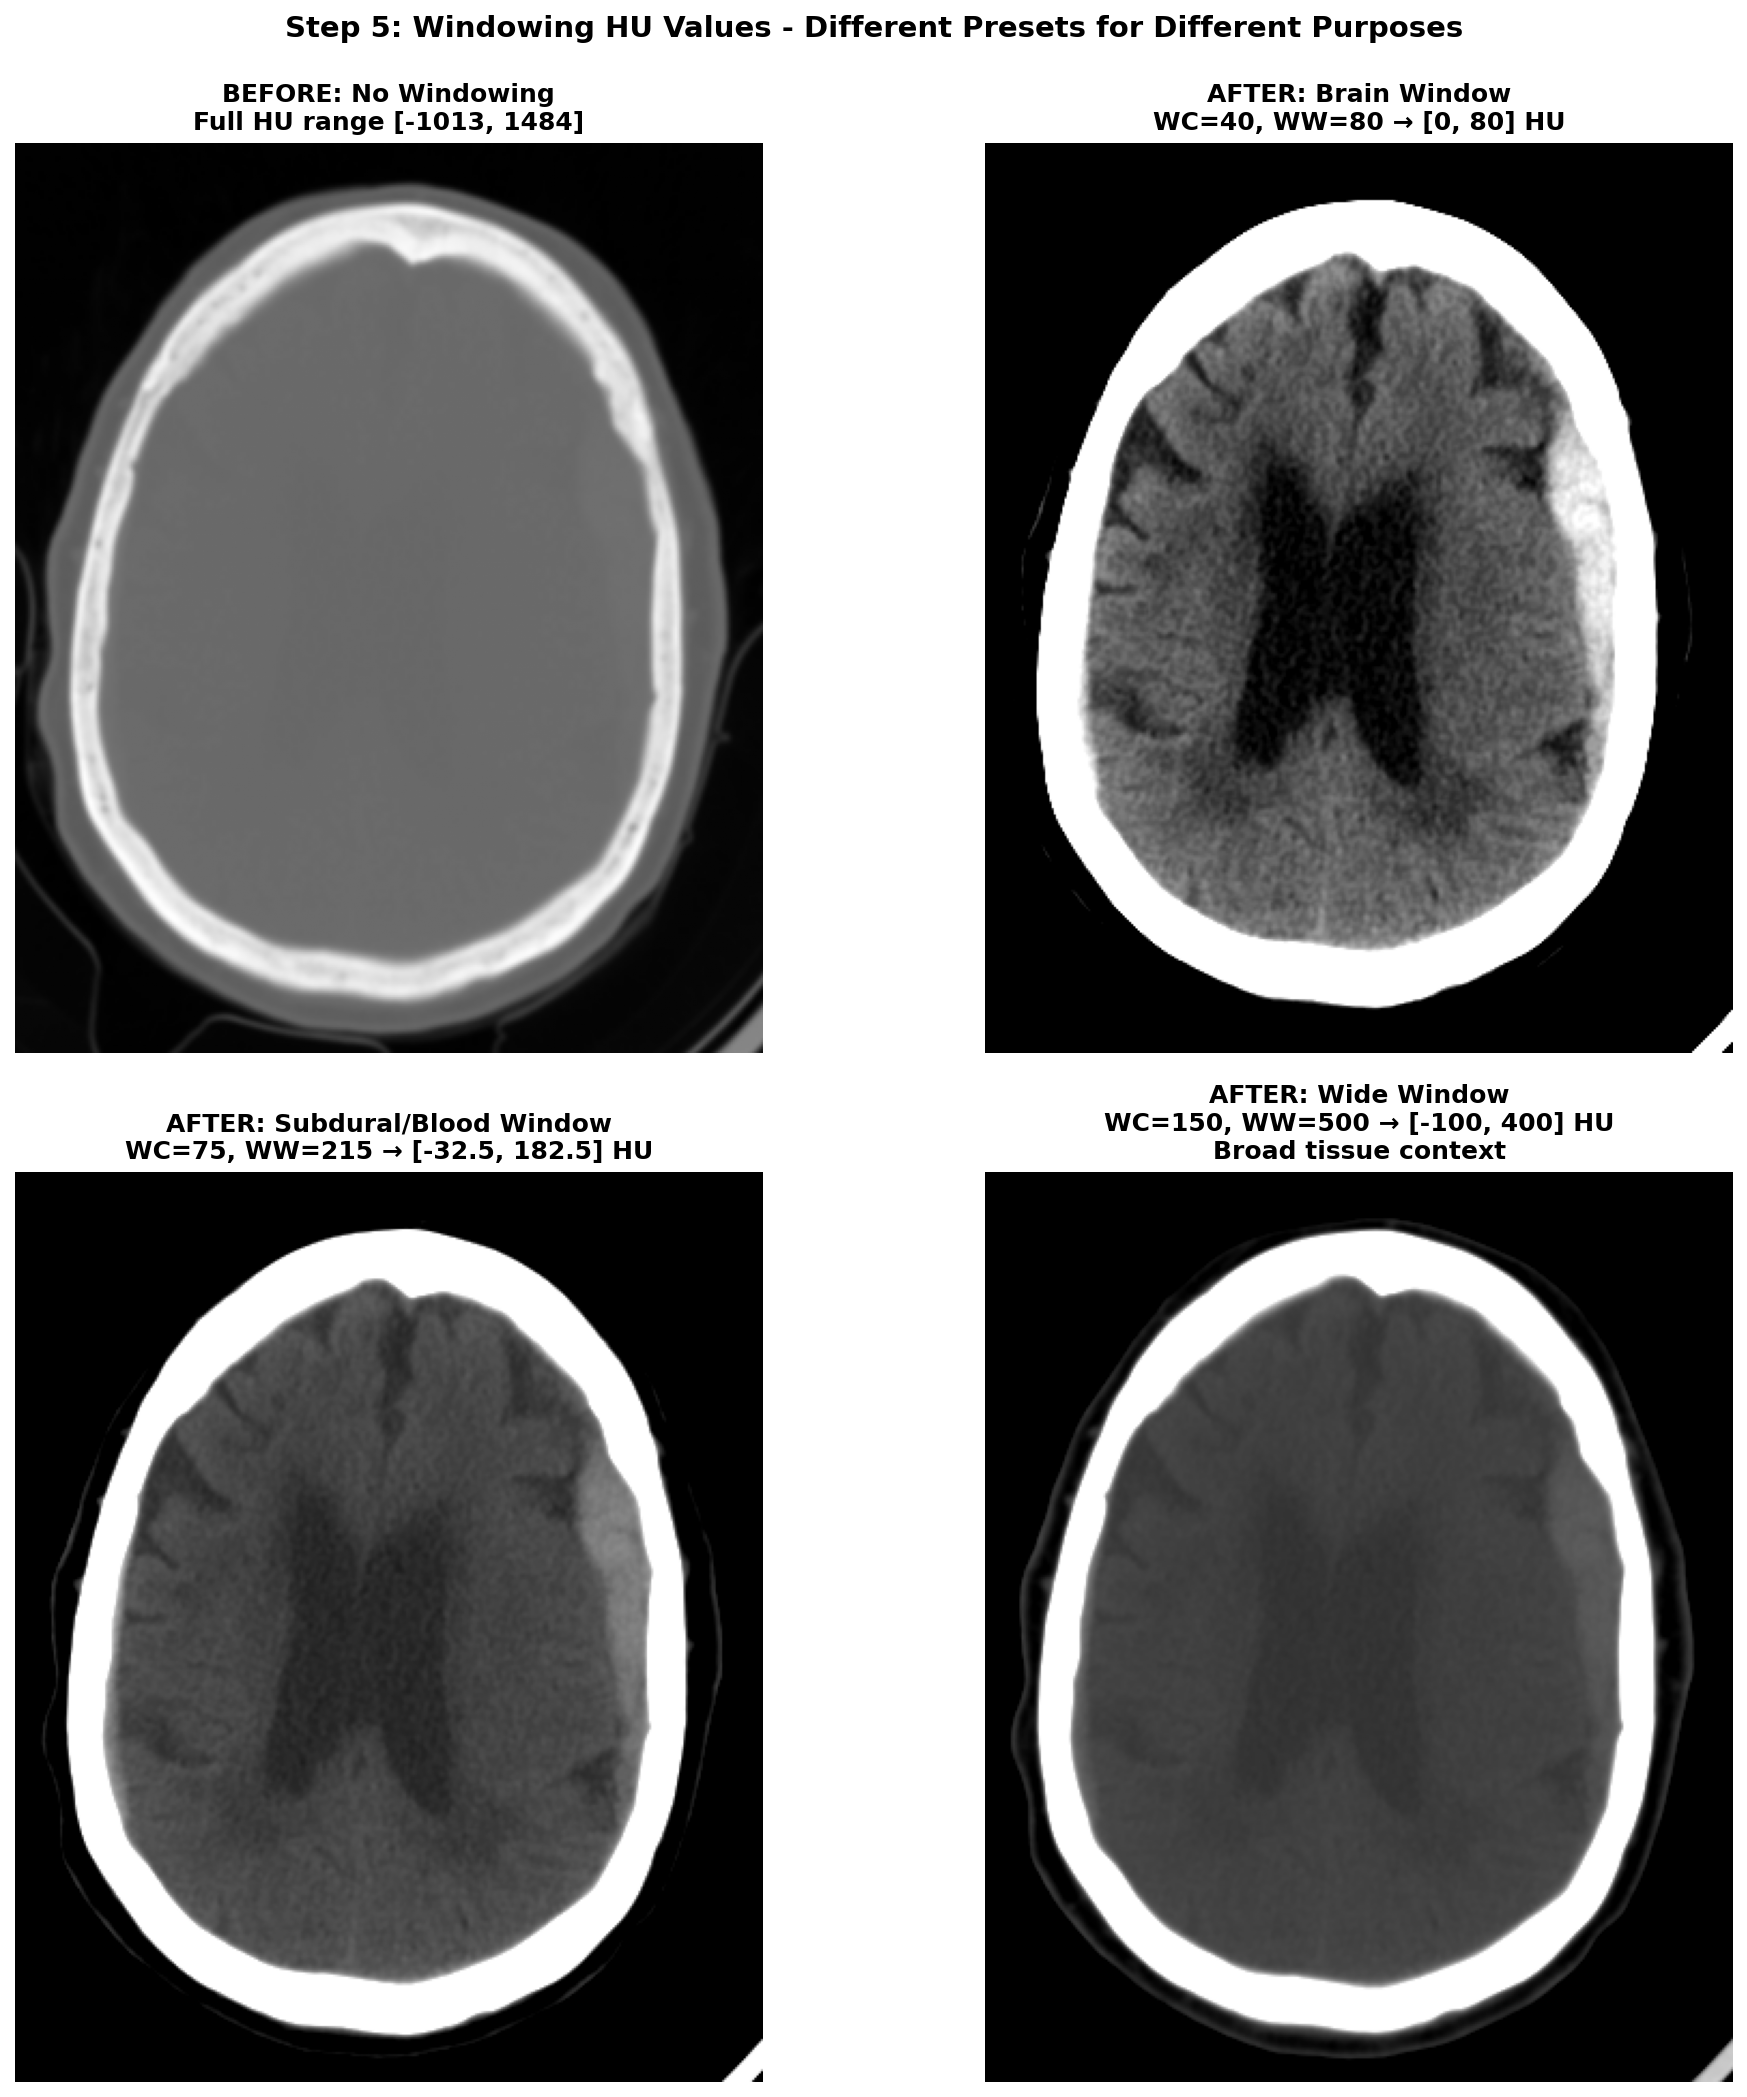

5) Windowing the range of Hounsfield Units (HU)

The HU scale is quite wide, ranging from -1000 HU for air to more than +1000 HU for dense bone. And in this wide range of value, only a small subset is really useful for brain CT scans analysis. The rest of the non-useful information can be considered as noise that can make the learning task harder for a deep learning model. Hence the need to restrict the range of HU values. This is achieved through a technique called windowing in medical imaging. Windowing involves selecting a range of Housefield Units values judged pertinent for the task at hand and remapping all values outside this range to the closest extremum of the range. The range is commonly defined by giving a window center (WC or WL) and a window width (WW). The range of HU values is then .

There are several standard window settings for different tissues and pathologies. The exact value can vary slightly between studies and articles but the most common ones for deep learning applications are:

-

Brain window (parenchyma) — WC = 40, WW = 80 → HU range

[0, 80]This is the standard brain window used clinically for evaluating brain tissues. -

Subdural / blood window — WC = 75, WW = 215 → HU range

[-32.5, 182.5](some studies also use WL 50-100, WW 130-300 for thin subdural detection). This enhances acute blood detection and thin subdural hematomas, providing better contrast for hemorrhagic pathology. -

Wide / raw window —

[-100, 400]→ preserves broad context including edema and most pathologic ranges while suppressing bone and air artifacts. This provides comprehensive tissue visualization without losing important diagnostic information.

Narrow windows (very small WW) are generally poor choices because they can amplify scanner noise so are a bit risky to use for deep learning applications.

After applying windowing to restrict the HU range, the data typically needs to be scaled for optimal neural network training. The most common scaling approach is a min-max normalization to [0, 1] range:

with and being the minimum and maximum HU values of the chosen window.

Applying multiple window settings to get multiple channels of input data can be a great idea to provide different level of information to the model. It can also be useful when leveraging pretrained 2D models that expect 3-channel input like RGB images. In this case, you can create a 3-channel input where each channel corresponds to a different window setting (e.g., brain window, subdural window, wide window). This way, you can utilize the rich information from multiple windows while still benefiting from transfer learning with pretrained models.

The effect of windowing is demonstrated below on our RSNA hemorrhagic stroke case. The left panel shows the full HU range (-1000 to +1000 HU) where bone appears very bright, making it difficult to distinguish subtle brain tissue variations. The middle panel applies the standard brain window (WC=40, WW=80, range [0, 80] HU), which optimally displays brain parenchyma and clearly highlights the hemorrhagic region as a bright hyperintense area. The right panel shows the subdural/blood window (WC=75, WW=215, range [-32.5, 182.5] HU), which is specifically designed to enhance blood detection and provides excellent contrast for the hemorrhage while still showing surrounding brain tissue.

When applying multiple windows to create multi-channel input (for example when using pretrained models expecting RGB input), here's what the different channels look like. Below we show our hemorrhagic stroke case with three different window settings applied simultaneously.